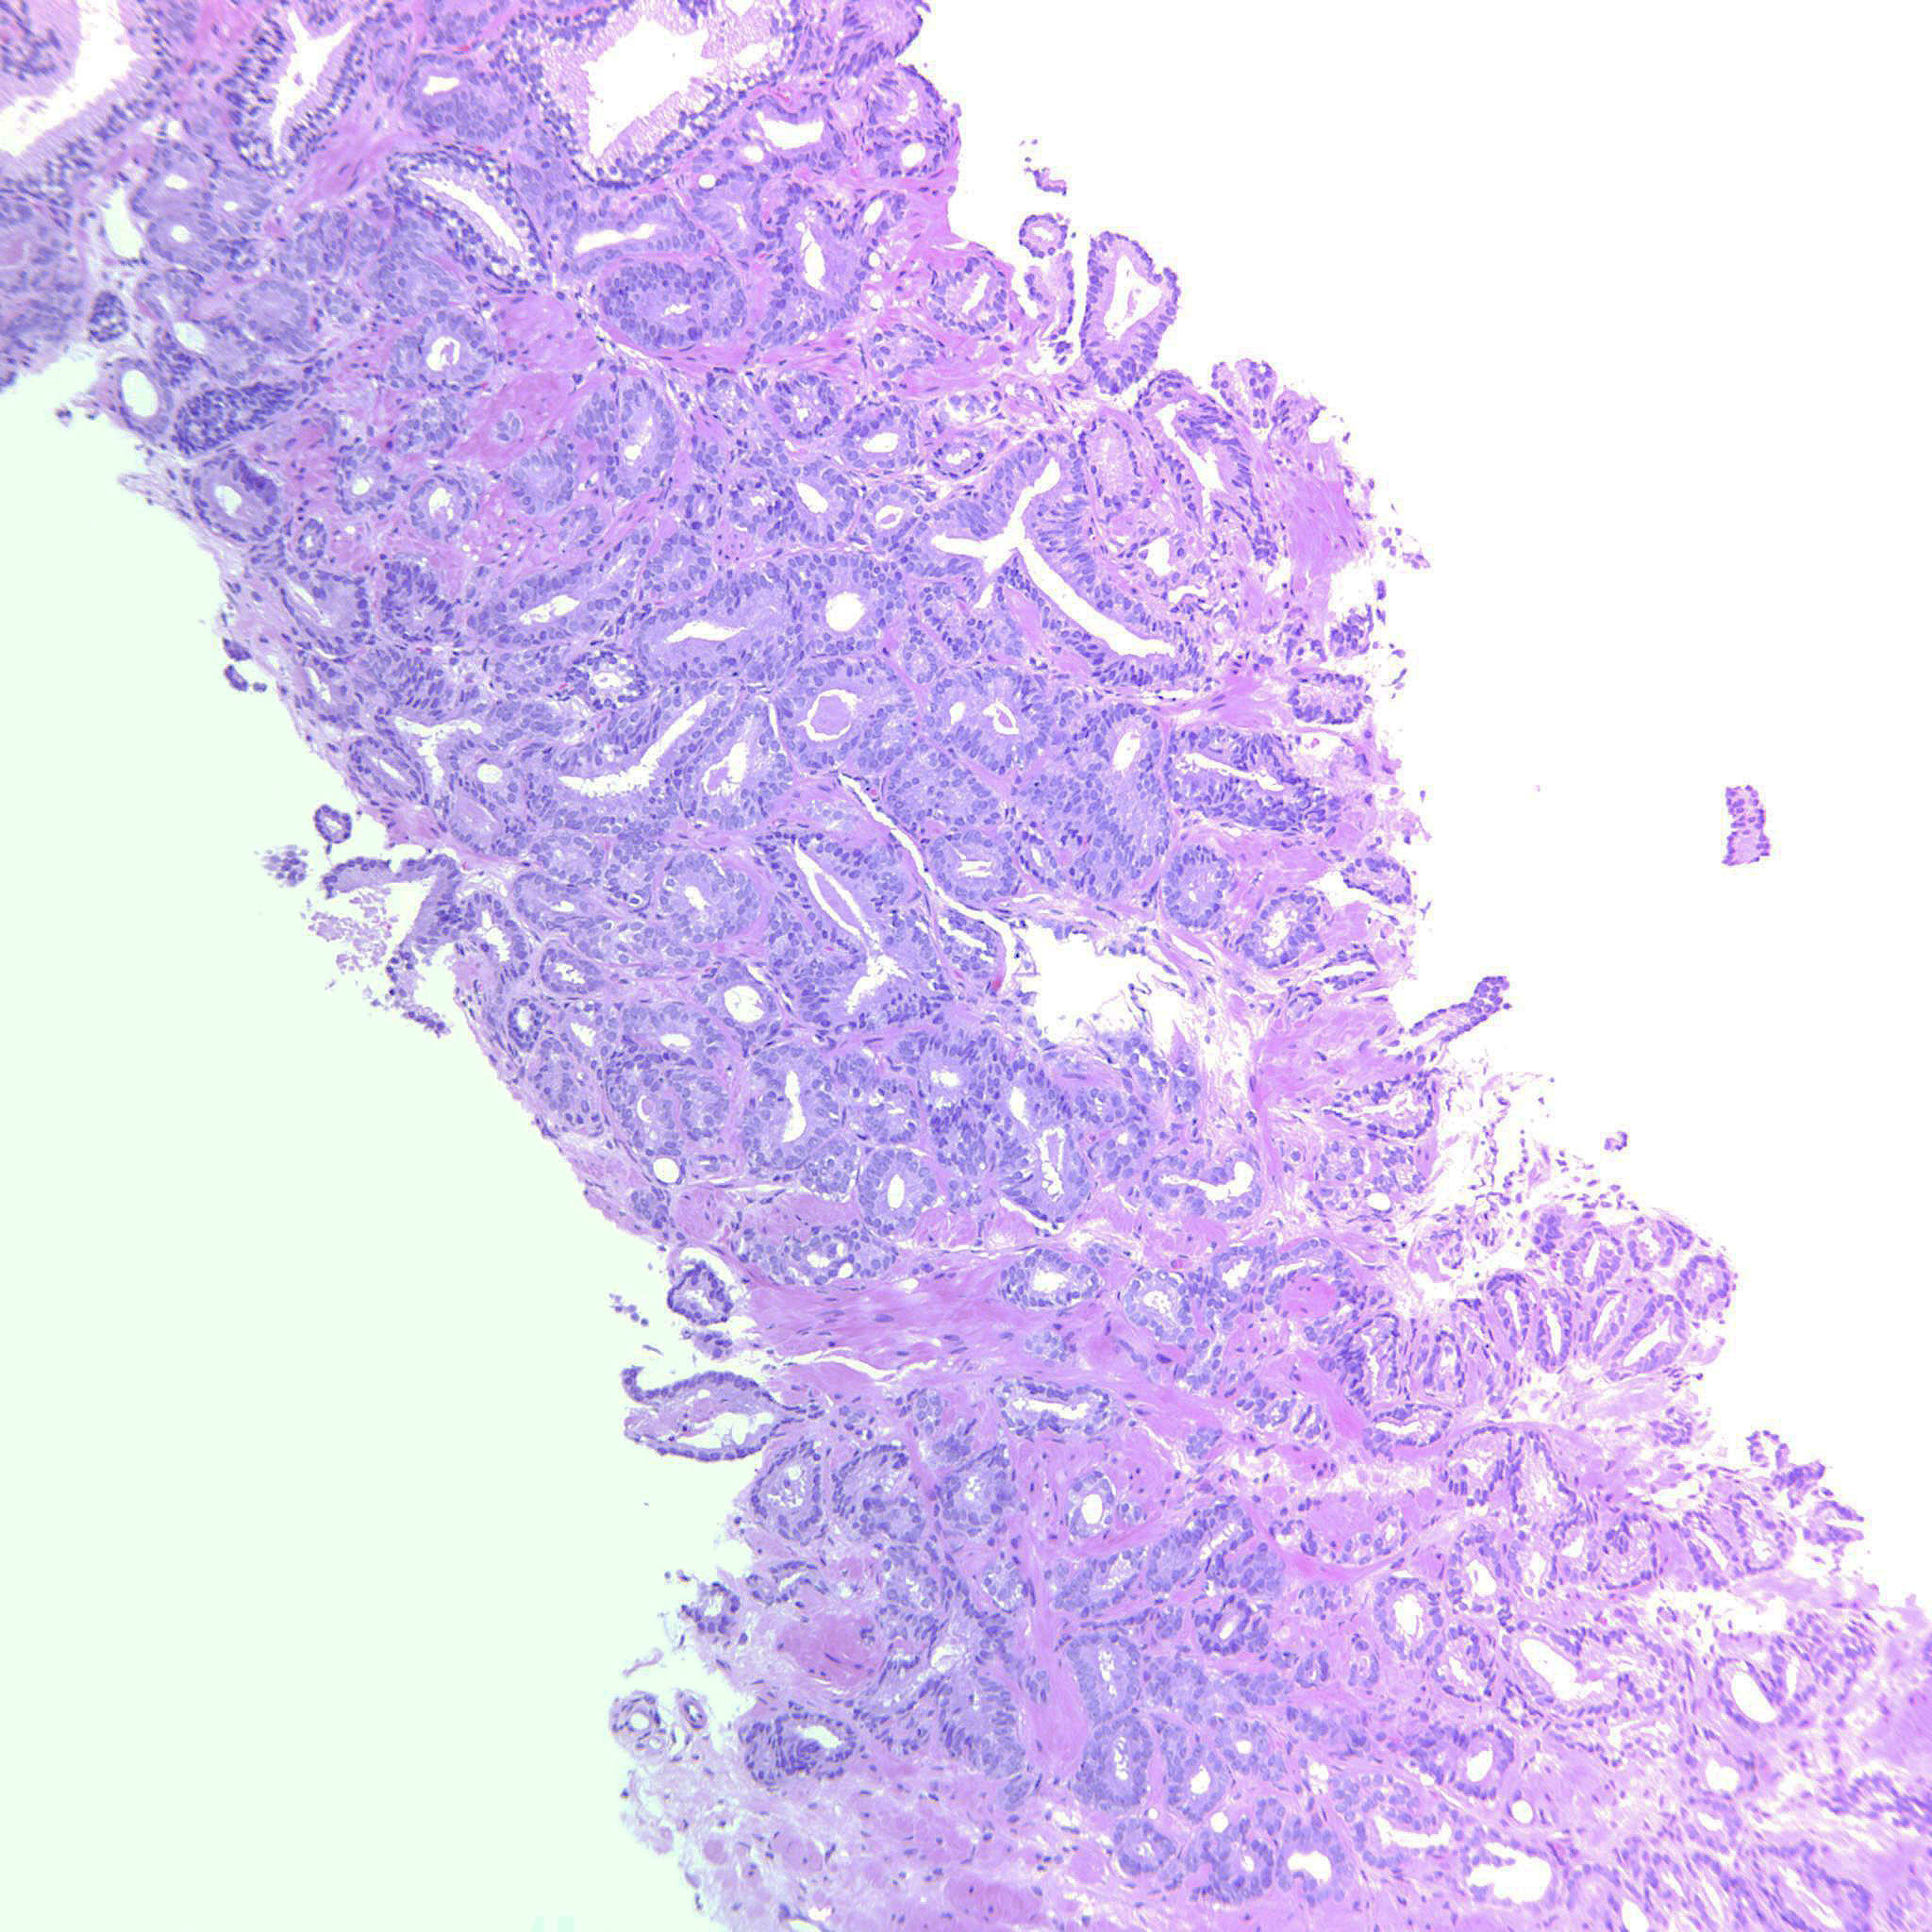

Prostate cancer grading

Case ID: 643